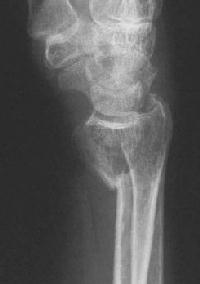

Clinical Example: Distraction plate fixation of distal radius fracture

distal radius fracture

distraction plate